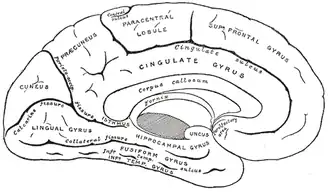

Several brain regions have been implicated in the neurological basis of flashbacks. The medial temporal lobes, the precuneus, the posterior cingulate gyrus and the prefrontal cortex are the most typically referenced with regards to involuntary memories.[18]

The medial temporal lobes are commonly associated with memory. More specifically, the lobes have been linked to episodic/declarative memory, which means the damage to these areas of the brain would result in disruptions to declarative memory system.[22] The hippocampus, located within the medial temporal regions, has also been highly related to memory processes. There are numerous functions in the hippocampus that includes aspects of memory consolidation.[14] Brain imaging studies have shown flashbacks activating areas associated with memory retrieval.[18] The precuneus, located in the superior parietal lobe, and the posterior cingulate gyrus, have also been implicated in memory retrieval. In addition, studies have shown activity in areas of the prefrontal cortex to be involved in memory retrieval.[18]

Thus, the medial temporal lobe, precuneus, superior parietal lobe and posterior cingulate gyrus have all been implicated in flashbacks in accordance to their roles on memory retrieval.[23]